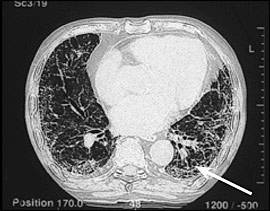

石綿症は繊維症肺疾患または塵肺です。そして、アスベスト繊維の吸入から生じる。多くの患者において、通常比較的マイナーな徴候をもたらす非常に軽くて痛みのない繊維症によって特徴づけられる。一般にピークのアスベスト暴露と診断の間の潜伏期間は20〜30年。身体検査における聴診のひび割れ音を伴う労作性呼吸困難の病訴は、更なる迅速な検査を促さなければならない。肺機能の初期の変化は、減少した拡散能力と労作性な酸素不飽和化であるかもしれない。より病気の過程が進展するのつれ、肺機能テストは、全肺気量と肺活量の減少と伴う、制限的パターンをとるだろう。胸部X線撮影は、一般的に増加した間質陰影としばしば胸膜プラークを示す。主に胸部のCT上の典型的検査結果は、増加した間質陰影を含む。後に蜂巣肺になることは明瞭かもしれない。(図1)多くの点で、石綿症は突発性肺繊維症と臨床的に類似している。しかし、石綿症は通常ゆっくり進行するが、突発性肺繊維症は急速に進行する特徴を持っている。

(図1);胸部CT画像

重症石綿症患者